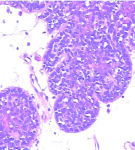

(1)表皮囊肿:是一种真皮内含有角质囊肿。系因外伤将表皮植入皮下而成。其囊肿壁为上皮结构,但基底细胞层为囊壁外层。角质层为囊壁内层并充满角质物于腔内。

5.表皮囊肿

较常见,好发生于青年,儿童,老年少见。正常皮色,圆形、有弹性,质略硬。囊壁为正常皮肤,囊腔内充满角质。可单发或多发,常发生于头皮、面部、颈及躯干。